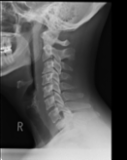

The severe cervical spine pain prompted an emergency MRI examination, which showed a clear prevertebral inflammatory soft tissue process. On close inspection, a calcific deposit anterior to the dens axis can already be suspected on MRI (especially T2 or axial T1fs Gd+). The calcium depot is only shown very fluffy on X-ray and CT, suggesting an acute stage with precipitation/resorption of the calcific milk.